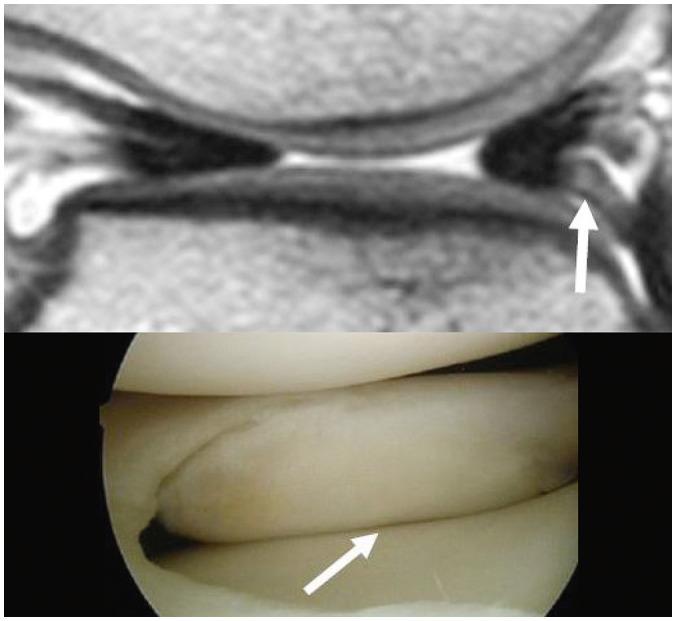

To accurately interpret knee MRI, it is important not only to know the basic meniscal anatomy but also to distinguish it from that under pathological conditions. Thus, it would be helpful to know the normal meniscus variants (false positives) that could be mistaken for meniscal tears, and tears that could easily be missed and incorrectly diagnosed as normal (false negatives). False positives include synovial recesses, meniscal flounce, the relationship between the popliteus tendon and lateral meniscus, transverse ligament, the anterior root of the meniscus, and meniscofemoral ligament. False negatives include focal radial tears, flap tears, posterior root tears, meniscocapsular separation, and discoid meniscal tears. In this pictorial essay, we reviewed the imaging data obtained in the aforementioned cases.

为了准确解读膝关节磁共振成像(MRI),不仅要了解半月板的基本解剖结构,还要将其与病理状态下的情况区分开来。因此,了解可能被误诊为半月板撕裂的正常半月板变异(假阳性)以及容易被漏诊并错误诊断为正常情况(假阴性)的撕裂情况会有所帮助。假阳性包括滑膜隐窝、半月板皱襞、腘肌腱与外侧半月板的关系、横韧带、半月板前根和半月板股骨韧带。假阴性包括局灶性放射状撕裂、瓣状撕裂、后根撕裂、半月板关节囊分离和盘状半月板撕裂。在这篇图文文章中,我们回顾了上述病例中获得的影像数据。